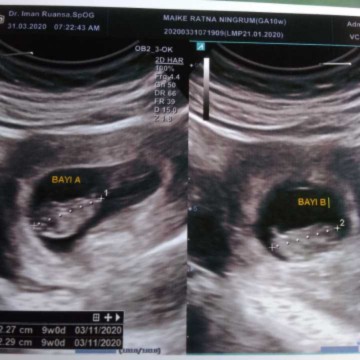

Bun saya sdang hamil kembar 32week, tapi perut bagian bwah sya udh mulai kram2 kyk mau haid dn jg pinggang bwh udh jg skit, tgl 1kmrn control kta dokter emg ad sedikit kontraksi, jd dsksih obat penguat nefidine dn preabor, smpe obtny udh abis skit ttp hilang timbul bun, malah ad rasa kayak dd nya itu melungsur kebawah kyk ngedorong it bun, ini kehamilan ke2 sya stelah prnh keguguran diusia kndungan 13minggu, jd blm ad pnglaman, kira2 d bunda yg ngerasain kyk bayiny ngedorong gt ngk ya bun, mksih sblmnya. #seriusnanya #jangandibully #firstbaby #PleaseAnswer